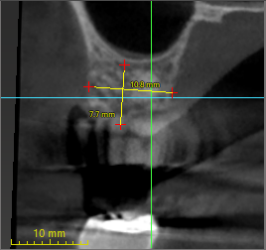

Hi all, Im trying to place a single unit #13. Due to boneloss, it looks like the buccal side is longer than the palatal side. If I were to place #13 completely submerged, 1mm subcrestal on the lingual side, it looks like it would be 2.2mm subcrestal on the buccal side. Should I shave down 1mm of the buccal bone to make it more even?

If so, do…